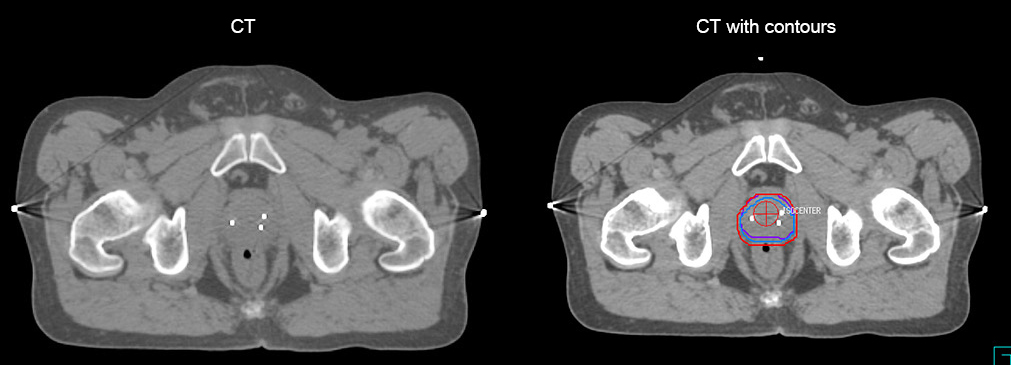

“The biggest problem for CT-based planning, especially in prostate, is you can’t see the cancer very well,” says Dr. Stevens. “On CT it can be quite challenging to see the edge of the prostate especially at the apex. When the edge of the prostate can’t be delineated well on CT, radiation oncologists will increase their margins a little bit so they don’t miss it, but that can also increase toxicity.” “Using MR, the prostate is well delineated. We quickly see the edges of cancerous tumors like in prostate cancer, and as normal structures can be defined, we can optimize the treatment plan to protect these organs and their normal function. This can potentially improve the outcome. And it improves workflow as well. We can contour more quickly, confident that the tumor is going to be in the field.” “The Ingenia 3.0T MR scanner provides high resolution allowing us to make scans fast for the patients. It also gives the potential to include methods like MR spectroscopy and diffusion weighted Imaging, which we’re in the process of doing right now,” Dr. Stevens adds.

“When a patient registers, first CT simulation and MR simulation are done, followed by CT-MR registration on Pinnacle3. Then the target and normal organ delineation is performed on MR images. Meanwhile we create a reference CT image for online treatment and localization correction. During the treatment phase we can perform additional MRI scans to visualize the anatomy changes and create an adaptive plan. This plan basically adapts the treatment plan to the changes.” “Along with its great benefits, MR has introduced some new challenges,” Dr. Stevens says. “Radiation therapy teams generally have no experience with MR. The Philips training helped us to implement fully the things we can do with the Ingenia MR-RT system. So the training, as well as having a good MR physicist, is critical.”